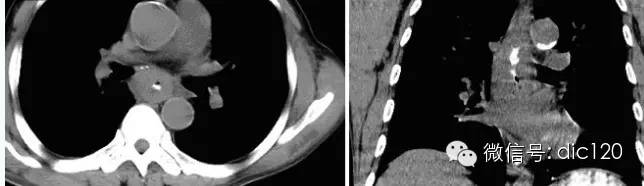

【病史臨床】男,63歲,胸痛,進行性吞咽困難伴消瘦20天。

【影像表現(xiàn)】 CT:表現(xiàn)現(xiàn)為食管壁明顯增厚,管腔狹窄;食管與周圍結(jié)構(gòu)分界不清食管吞鋇:食管中段充盈缺損,管腔不規(guī)則狹窄,管壁僵硬,粘膜糾集破壞,與正常食管壁分界清晰。

【診斷】 病理診斷:食管(中下段)高-中分化鱗狀細胞癌,侵及食管壁全層。(圖1.2)